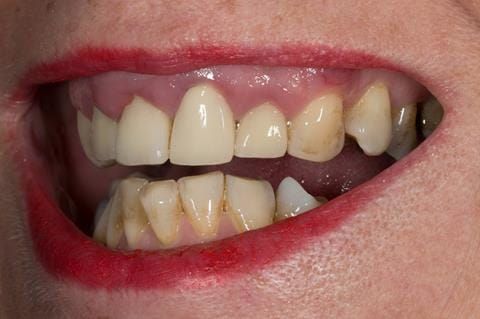

- High smile line showing gum above gingival zeniths of upper front teeth when smiling. Aesthetic failure of the upper four incisors with inflammation of the gingivae and mis-match of the gingival zenith levels.

- Other than the maxillary incisors the remaining dentition was in marginally better condition being moderately to heavily restored. Many will probably require replacement and restoration from time to time mainly from wear and tear owing to occlusal forces.

Following consultation and second discussion appointment the patient chose to have option 3 namely, a maxillary cobalt chromium based partial denture/protective occlusal splint. The clinical situation and treatment process is shown in detail below with photographs. The patient was successfully rehabilitated with this and her quality of life considerably improved. The clinical work was provided by Finlay and the technical work by Rowan.